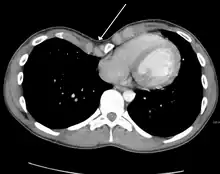

Physiologically, increased pressure in utero, rickets and increased traction on the sternum due to abnormalities of the diaphragm have been postulated as specific mechanisms.[9] Because the heart is located behind the sternum, and because individuals with pectus excavatum have been shown to have visible deformities of the heart seen both on radiological imaging and after autopsies, it has been hypothesized that there is impairment of the function of the cardiovascular system in individuals with pectus excavatum. While some studies have demonstrated decreased cardiovascular function, no consensus has been reached based on newer physiological tests such as echocardiography of the presence or degree of impairment in cardiovascular function. However, a 2016 meta-analysis found significant evidence that surgical correction of pectus excavatum improves patient cardiac performance.[14]

Many scales have been developed to determine the degree of deformity in the chest wall. Most of these are variants on the distance between the sternum and the spine. One such index is the Backer ratio which grades severity of deformity based on the ratio between the diameter of the vertebral body nearest to xiphosternal junction and the distance between the xiphosternal junction and the nearest vertebral body.[17] More recently the Haller index has been used based on CT scan measurements. An index over 3.25 is often defined as severe.[18] The Haller index is the ratio between the horizontal distance of the inside of the ribcage and the shortest distance between the vertebrae and sternum.[19]

Chest x-rays are also useful in the diagnosis. The chest x-ray in pectus excavatum can show an opacity in the right lung area that can be mistaken for an infiltrate (such as that seen with pneumonia).[20] Some studies also suggest that the Haller index can be calculated based on chest x-ray as opposed to CT scanning in individuals who have no limitation in their function.[21]